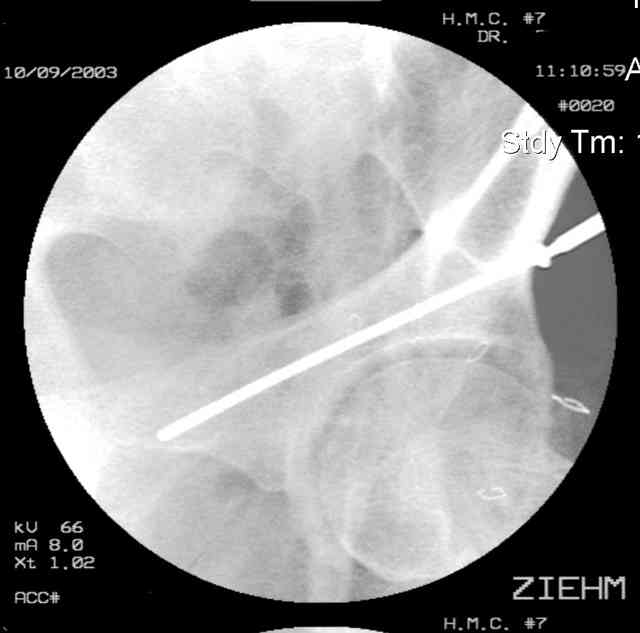

Prone Inlet

OK, now we're inserting the drill percutaneosuy using a sleeve. This fluoro shot is not for this patient (notice no clamp) but I was too lazy to go searching the PACS for one with the clamp on, so pretend...I'll save the next ones and send along...the imaging is the same and the clamp doesn't obstruct imaging other than very rarely...you can always tilt the C-arm a bit to clear it if the clamp obstructs the exact spot that you'd like to see. We'll assume that everyone knows the safe zone for a medullary ramus screw. Use a calibrated drill and sleeve of known length to simplify your life...or use Alex's fancy cannulated screws...I like 3.5mm screws because the oscillating 2.5mm drill bounces and remains intraosseus when it oscillates and contacts endosteal cortical ramus... so will the screw, and like a long bent screw IF the fracture is clamped... if unclamped, when the screw contacts the endosteum, it pushes the reduction apart instead of bouncing. The big 7mm cannulated screws fit few patients and extrude...we very rarely use them any more...you'll see an old one later.